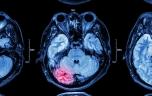

Tumeurs du cerveau : le mal de tête persistant peut être un signal d’alerte

Les signes cliniques (maux de tête persistants, déficit d’une fonction neurologique ou crise d’épilepsie à début focal) alertent le médecin qui prescrit la réalisation d’une IRM cérébrale. Cet examen d’imagerie permet de visualiser la tumeur. Un scanner cérébral est aussi réalisé pour compléter le diagnostic.